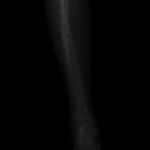

ペルシャ猫 11ヶ月齢 雄

他院にて左大腿骨遠位の成長板骨折(salter-harrisⅠ型)が認められており、治療相談を目的として来院。当院にて、キルシュナーワイヤーを用いたピンニングにより骨折部位の整復を行いました。術後の経過は良好で、現在も経過観察中です。

術前レントゲン